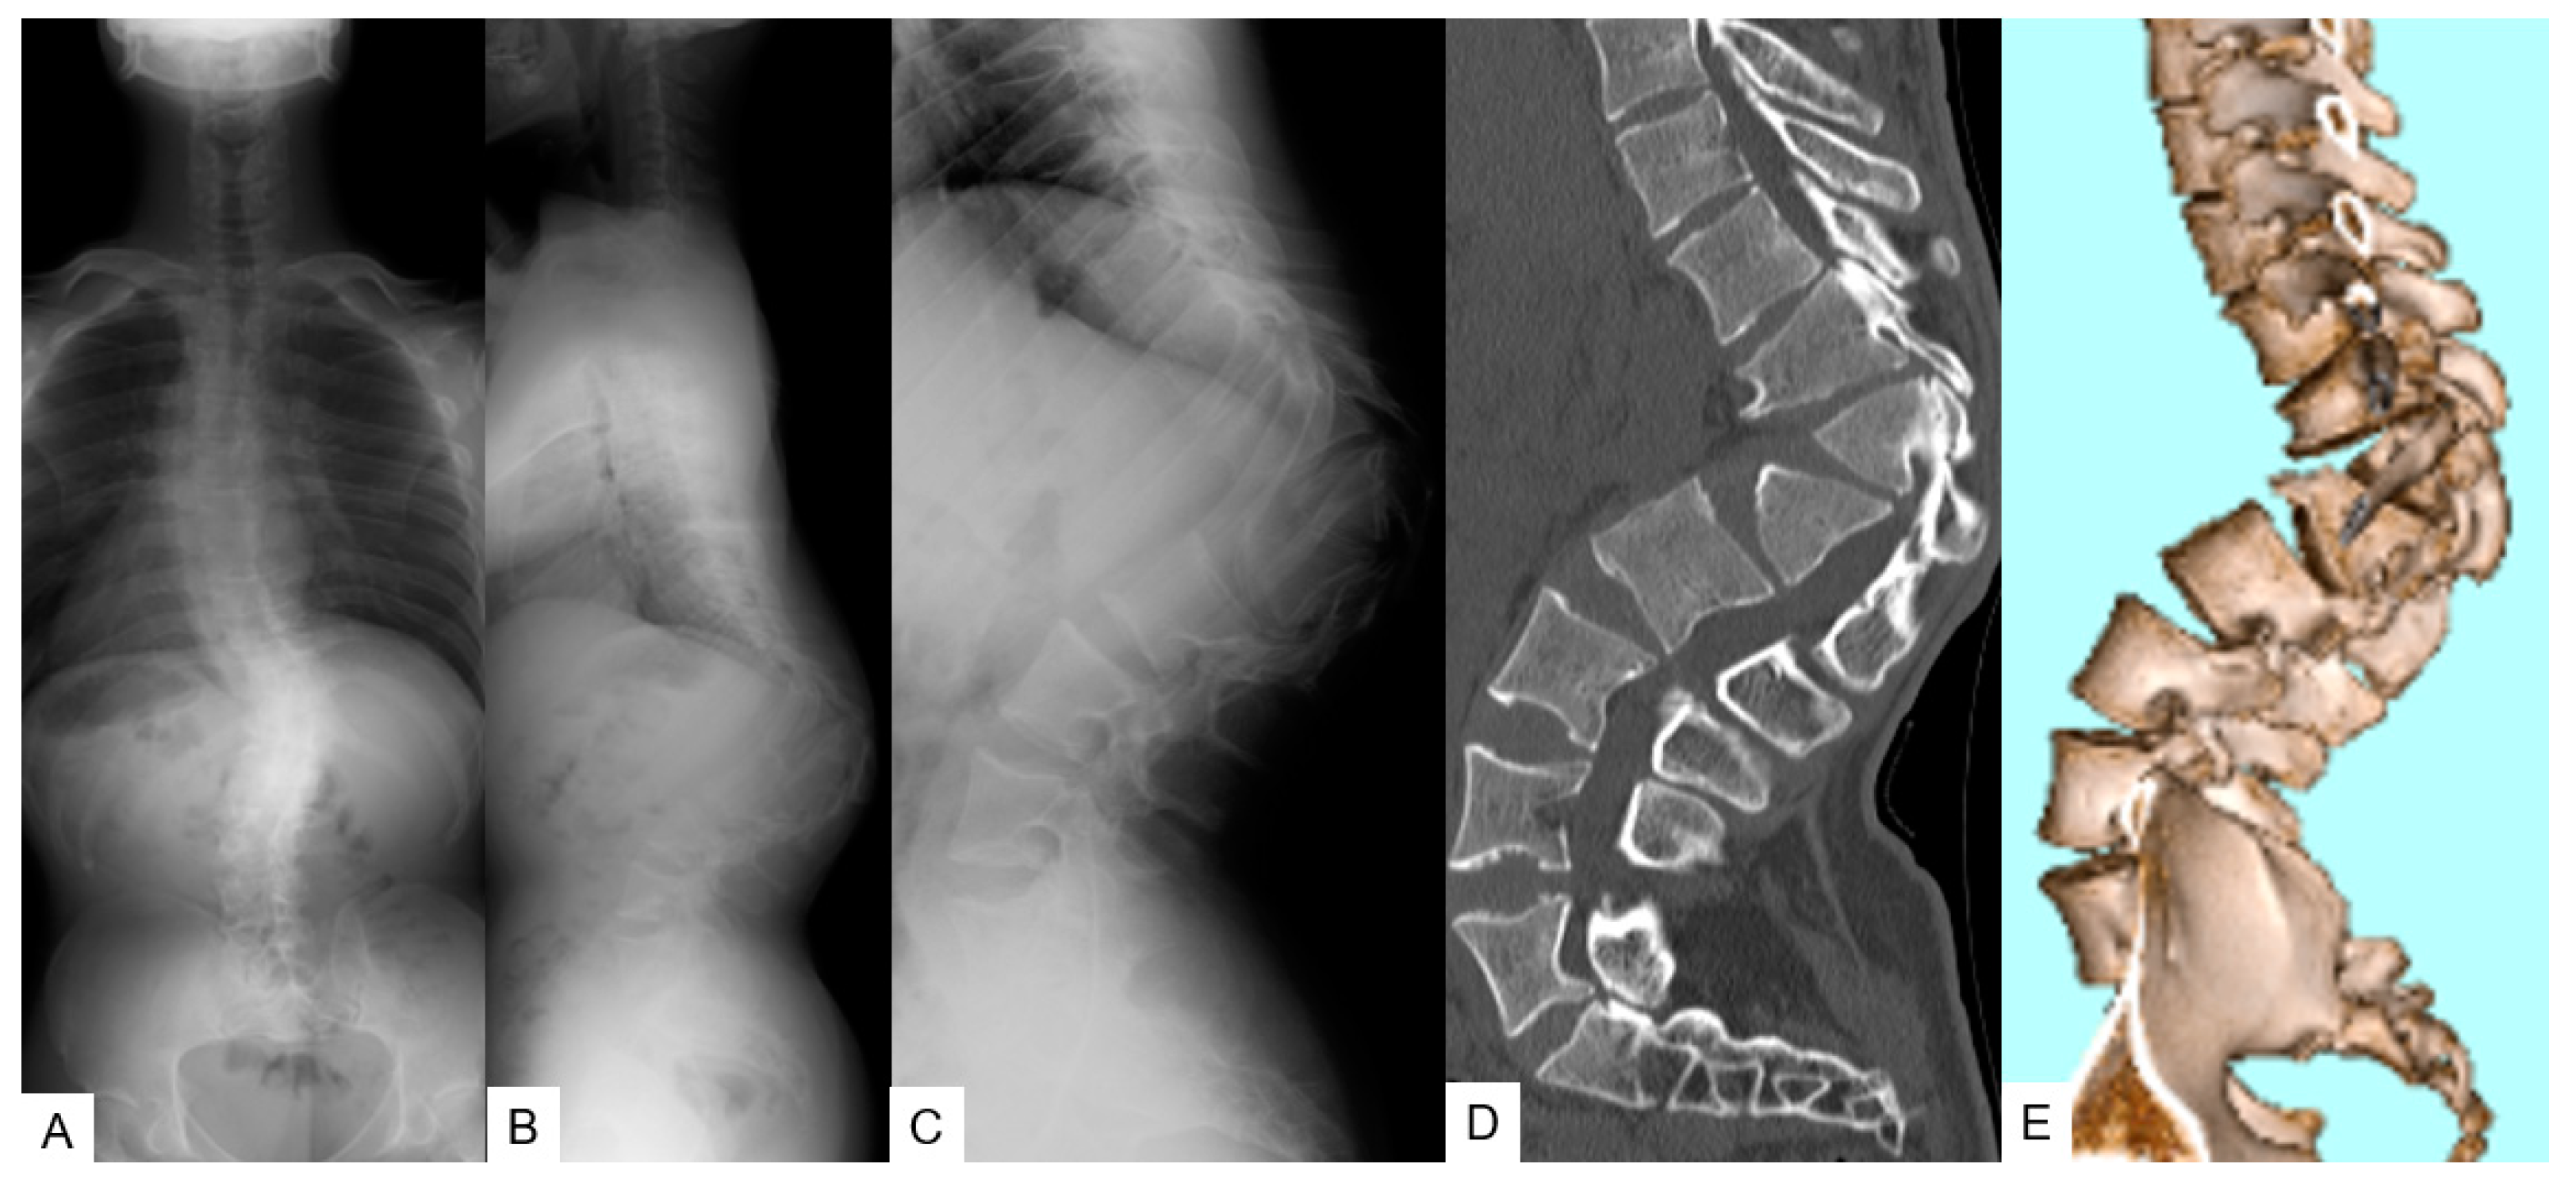

3.1.3. Preoperative Imaging

3.1.4. Surgery